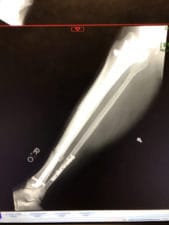

I broke my leg in four places and smashed my nasal cavity eight weeks ago today when a wind gust shoved me violently off my feet and into a rock field on Twin Sisters Peak.

Jim Davidson, SAR teams plus Rangers from RMNP demonstrating the highest levels of knowledge, professionalism and compassion got me to hospitals where after two surgeries, I am now recovering. My last update was four weeks ago so time for another update.